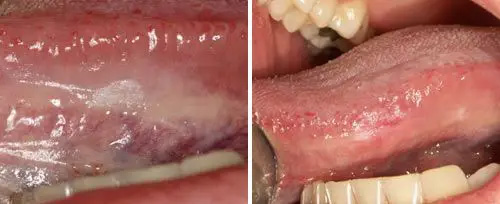

Leukoplakia Treatment